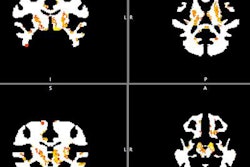

The project began in March and is still in its initial stages. Teams at the DOE and USCF are continuing to work on the connectome -- a model of the structural connectivity of the human brain. Meanwhile, scientists at the LBNL and ANL are focusing on data analytics, including genetic information and CT scans of TBI patients, according to the LLNL.